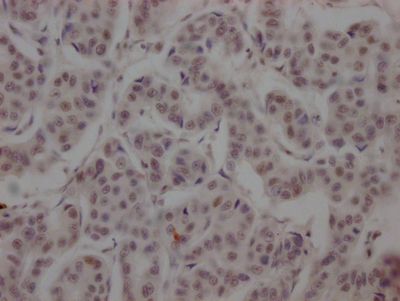

ApplicationELISA, WB, IHC; Recommended dilution: WB:1:500-1:5000, IHC:1:50-1:200